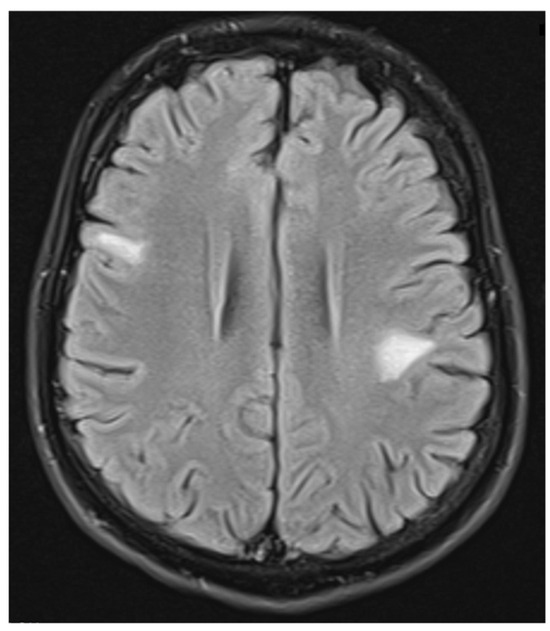

Figure 5.

FLAIR image of brain magnetic resonance imaging in the transverse plane showing a demyelinating focus in the right hemisphere of the cerebellum, including its peduncle (March 2022).

ADEM recurrence was recognized. The patient received immunoglobulins (2.0 g IV). After rehabilitation, an improvement in the neurological condition was observed over the next four weeks. The boy returned to school. Subsequently, he reported visual acuity disturbances in the left eye. Therefore, he was hospitalized in the neurology department. On admission, neurological examination showed horizontal nystagmus, lack of abduction in the right eye, dysarthric speech, and cerebellar syndrome. Brain MRI revealed numerous foci of increased signal on T2-weighted and FLAIR sequences, with the largest one occurring in the right cerebellar hemisphere accompanied by the involvement of the peduncle (Figure 5 and Figure 6) and bilateral involvement of the dentate nuclei of the cerebellum. Foci of increased signals on T2-weighted and FLAIR sequences were also found on MRI of the cervical and thoracic spine, meeting the LETM (longitudinally extensive transverse myelitis) criteria (Figure 7). Moreover, an orbital MRI showed “the left optic nerve was thickened to 3–4 mm, with increased T2 signal intensity indicating inflammation; the optic chiasm and right optic nerve were normal” (Figure 8). Again, positive serum anti-MOG antibodies were found in a clear titer of 1:100, while anti-AQP4 antibodies tested negative. Recurrent MOGAD was diagnosed based on the overall picture, and immunoglobulins were administered (a total dose of 2.0 g IV for five days). Oral azathioprine was included in the chronic treatment at a dose of 2 mg/kg body weight and oral methylprednisolone at a dose of 1 mg/kg body weight. After ten weeks (May 2022), right optic neuritis occurred during an attempt at withdrawing glucocorticosteroids. Methylprednisolone was reintroduced at a dose of 5 × 1.0 g intravenously. An MRI of the head revealed two new subcortical foci: one located in the right frontal lobe measuring 13 × 7 mm and another in the left parietal lobe measuring 19 × 14 mm (Figure 9). Additionally, the right optic nerve exhibited blurred outlines (Figure 10) and an increased signal in the central area, along with a marginally enhancing focus in the middle part of the right optic nerve measuring 2 mm in diameter. An ophthalmological consultation was conducted, revealing color vision deficiencies in the right eye across all axes, with no reading capability in the left eye. An OCT examination showed that the retinal nerve fiber layer (RNFL) in the right eye was normal (higher than a month earlier, suggesting a possible inflammatory process), while the left eye exhibited significantly reduced RNFL and ganglion cell count. Atrophy of the left optic nerve was diagnosed. Based on the clinical presentation, recurrent optic neuritis was diagnosed as a manifestation of another MOGAG, correlating with the onset of right optic neuritis following the discontinuation of methylprednisolone. Therefore, a decision was made to increase the dose of azathioprine to 2.5 mg/kg body weight and to maintain methylprednisolone for the following weeks. After the diagnosis of MOGAD with a typical radiological and clinical picture (ADEM, MDEM, recurrent ON) and the initiation of chronic immunosuppressive treatment, no more epileptic seizures were observed. It was decided to discontinue antiepileptic drugs, starting with gradual valproic acid.